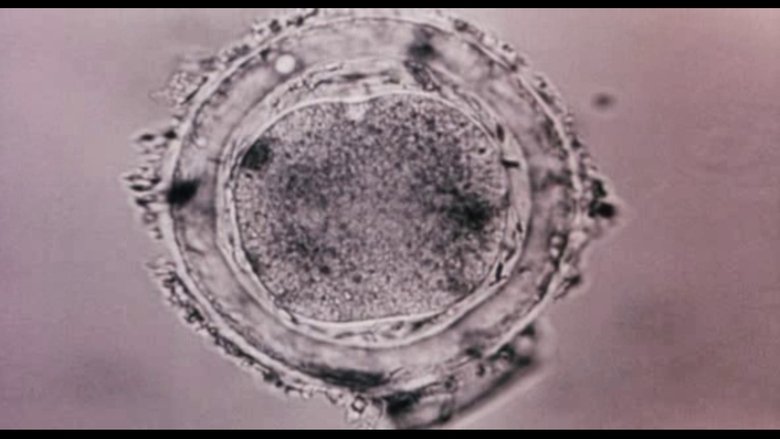

Bodysong документальный